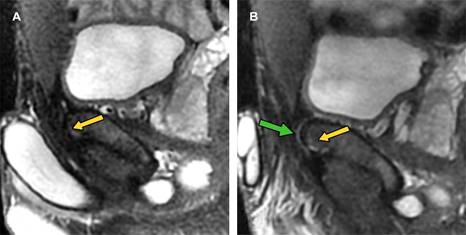

Se realizó ultrasonido inguinal y radiografía anteroposterior de pelvis las cuales no mostraron alteraciones; posteriormente, se decidió realizar resonancia magnética de pubis: en plano coronal (Figura 1) se observó fractura vertical en el cuerpo del hueso púbico izquierdo (flecha blanca en A y B) con edema de tejidos blandos adyacente (asterisco en A y B); en plano axial (Figura 2) se identificó fractura en la porción anterior del cuerpo del hueso púbico izquierdo (flecha blanca en A y B), existe osteítis púbica bilateral de predominio izquierdo (asterisco en A y B) y en plano sagital (Figura 3) se observó edema óseo a nivel de la placa aponeurótica del recto abdominal y aductor largo bilateral (flecha amarilla en A y B) de predominio izquierdo; además de desgarro en la placa aponeurótica izquierda (flecha verde).

Figura 3: Resonancia magnética de pubis. A) STIR plano parasagital derecho. B) STIR plano parasagital izquierdo. Se observa edema óseo a nivel de entesis de la placa aponeurótica del recto abdominal y aductor largo en ambos lados (flechas amarillas en A y B) de predominio izquierdo; además se observa pequeño desgarro en la placa aponeurótica izquierda (flecha verde en B).